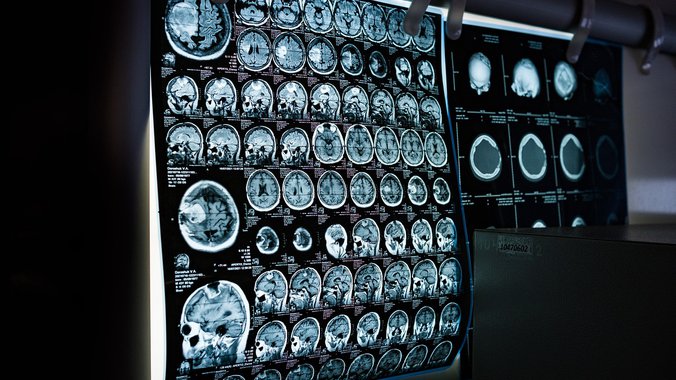

Naučnici sa Univerziteta Merilend otkrili su da krvna grupa može uticati na rizik od ranog ishemijskog moždanog udara, koji nastaje zbog blokade krvotoka u mozgu.